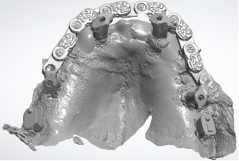

After concluding the surgical phase, the implant scan bodies were connected to the implants and merged together with the universal scan template (Designed by Dr Andrea Papa, produced by LaStruttura S.p.A., Cassano Magnago, Italy), in order to ease the scanning procedure in case of altered or bleeding mucosa (Figure 5). The scan started from the skeletal scan bodies to allow the software to correlate the pre-surgucal and post-surgical scans obtaining a perfect relation with the opposing arch (Figure 6).

Figure 5: Post-surgical digital impression including the skeletal scan bodies, the implant scan bodies and the universal scan template.